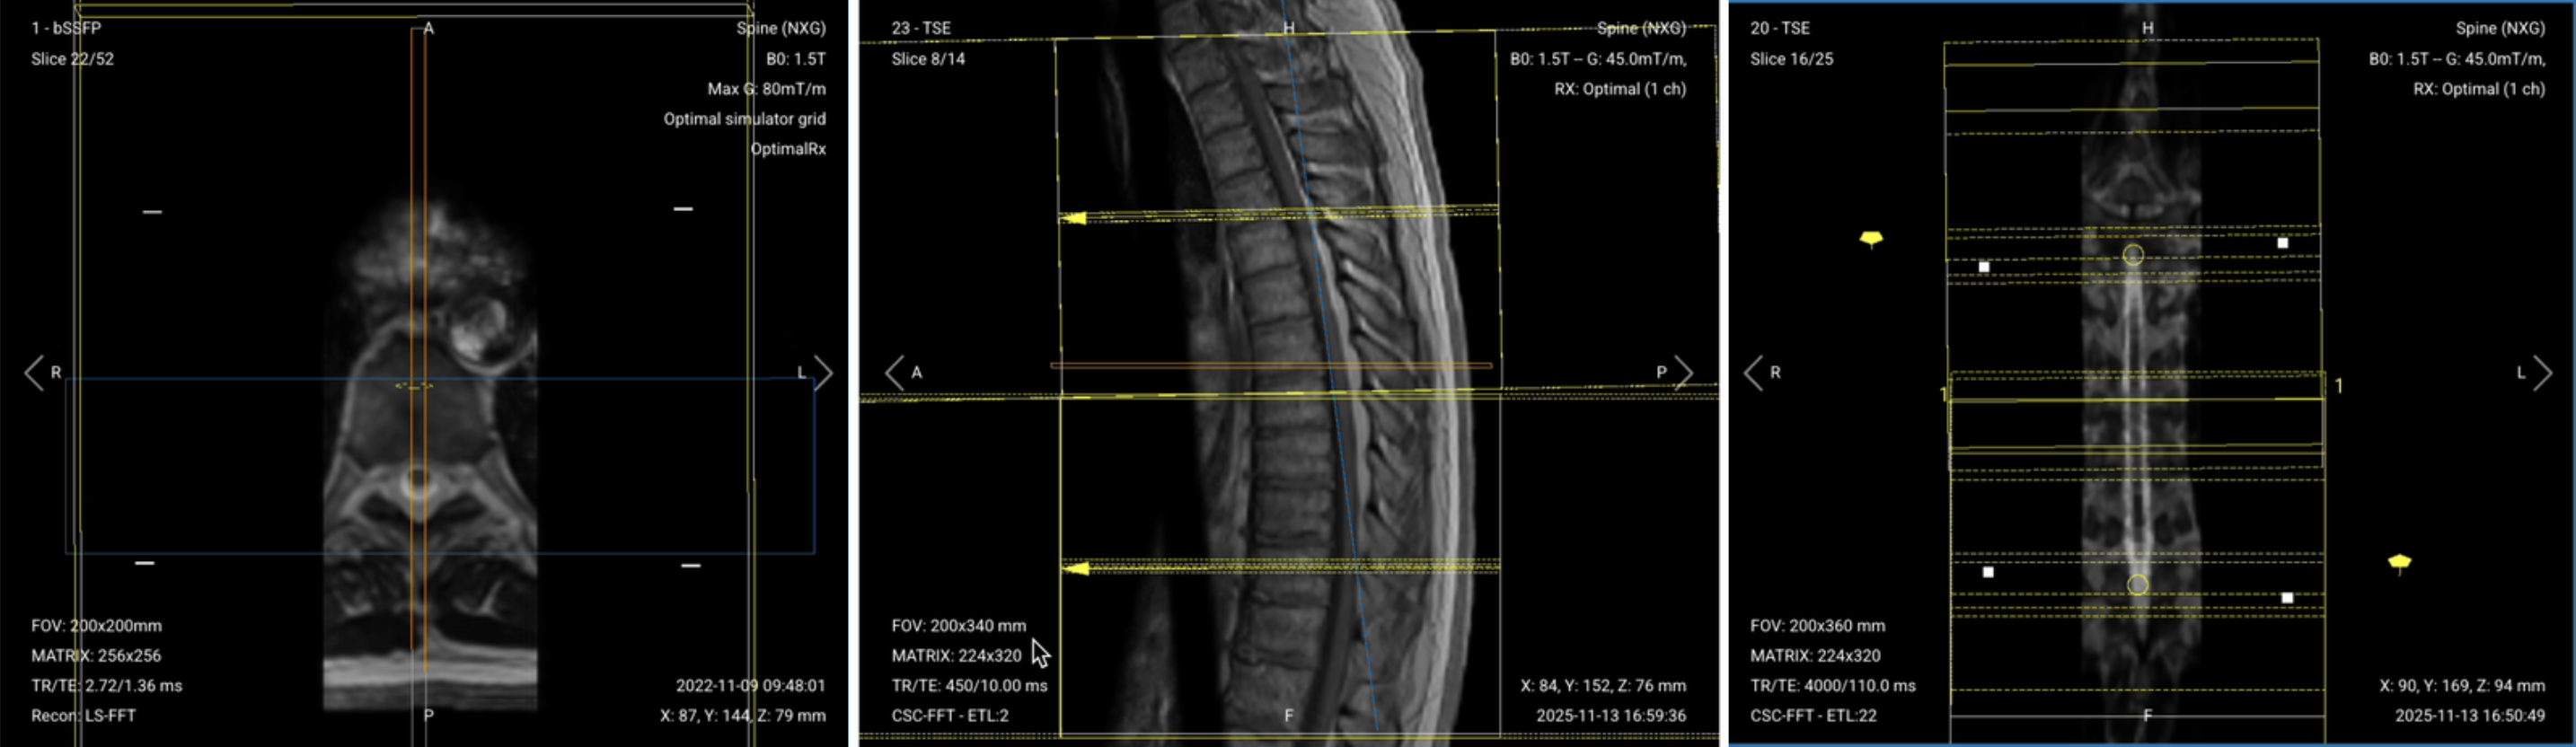

✅ Correct Planning:

.png)

Planning Instructions:

Parameters for Sagittal T1 TSE:

| Parameter | Recommended Values | Why These Values |

|---|---|---|

| Echo Time (TE) | 10–20 ms | Shorter TE is required for T1 contrast. |

| Repetition Time (TR) | 400–600 ms | Shorter TR is required for T1 contrast. |

| Field-of-View (FOV) | 200 × 340 mm | Rectangular FOV optimized for the thoracic spine's vertical extent, covering superior-to-inferior while minimizing anterior-posterior to reduce scan time. |

| Matrix | 224 × 320 | Medium matrix size provides sufficient resolution while maintaining short scan time and high SNR. |

| Foldover Direction (Phase) | Foot-to-Head (FH) / Superior-to-Inferior | Aligns with cerebrospinal fluid flow to reduce flow artifacts. |

| Number of Slices | 14–18 | Covers the thoracic spine from right to left adequately. |

| Slice Thickness | 4 mm | Medium thickness provides good resolution without increasing scan time too much. |

| Slice Gap | 0.4 mm | 10% of slice thickness prevents crosstalk while maintaining continuity. |

| NEX / Averages | 1–2 | Provides adequate SNR while keeping scan time reasonable. |

| Turbo Factor / ETL | 2–3 | Low turbo factor minimizes T2-weighting and preserves pure T1 contrast. |

| Bandwidth | 50,000 Hz | Medium bandwidth balances SNR with chemical shift artifact reduction. Lower than typical values to improve SNR in the challenging thoracic region. |

| Fold-over Suppression | Yes | Prevents wrap-around artifacts. |

| Saturation Bands | Yes | Placed anterior to the spine to suppress cardiac, respiratory, and vascular motion artifacts. |

Parameters for Axial T2 TSE: